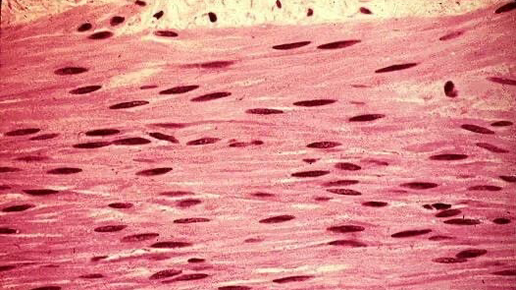

Гладкая мышечная ткань. Строение гладкой мышечной ткани.

Гладкая мышечная ткань находится в стенках внутренних органов, сосудов и в составе желез и кожи, состоит из мышечных клеток веретиновидной формы - гладких миоцитов. Сокращается помимо нашей воли, то есть является непроизвольной. Гладкая мышечная ткань делится на висцеральную и сосудистую. в дефинитивном состоянии в гладкой мышечной ткани клеточная регенерация в виде размножения миоцитов полностью не прекращается. Существуют данные о том, что пролиферация и дифференцировка в большей степени свойственна субпопуляции малых (по размерам) гладких миоцитов...